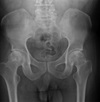

43

Give 3 differentials in order of likelihood.

(Erlenmeyer flask deformity) 1. Thalassemia 2. Sickle cell anemia 3. Osteopetrosis

44

Give 2 differentials in order of likelihood.

1. Thalassemia 2. Sickle cell anemia

What is demonstrated in the right ilium?

Hemophiliac pseudotumor (geo. Lytic lesion)

48

What is occurring medial to the left hip?

Myositis ossificans